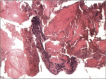

Non-traumatic myositis ossificans circumscripta at elbow joint in a 9-year old child

Myositis ossificans circumscripta (MOC) is a kind of self-localized, benign and tumor-like lesions often seen in adults, with approximately 75% of cases caused by trauma. We reported a case of non-traumatic MOC occurred at the elbow joint in a 9-year old child and it has been excised by surgery. After 18 months follow-up, a favorable outcome has been achieved with the Broberg-Morrey score of 100. We suggest that surgical resection should be done as soon as the diagnosis is confirmed.